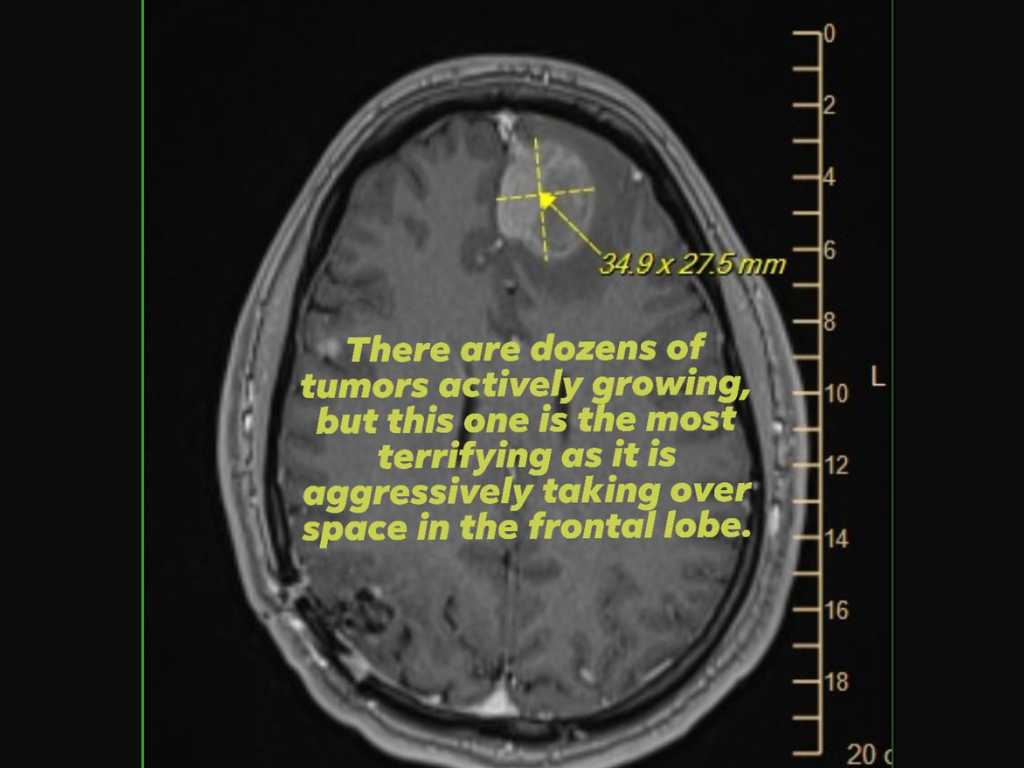

Однако одна из историй, связанных с увольнениями, вызвала особый резонанс. Среди сокращенных оказался сотрудник компании Майкл Принке, проработавший в Epic Games почти семь лет. Его жена Дженни Гриффин рассказала в соцсетях, что мужчина борется с терминальной формой рака мозга, и потеря работы привела к немедленному прекращению его страхования жизни.

По ее словам, из-за уже существующего заболевания оформить новую страховку невозможно, что поставило семью в крайне тяжелое положение. Женщина выразила обеспокоенность тем, как ей справляться с финансовыми обязательствами и обеспечивать будущее ребенка.

Она подчеркнула, что ее муж — не просто уволенный сотрудник, а отец и супруг, и призвала руководство компании обратить внимание на ситуацию. При этом медицинская страховка, покрывающая лечение, будет действовать еще шесть месяцев.